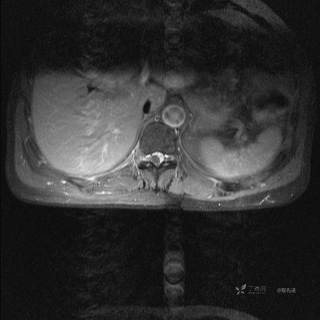

MR

T2

T2压脂

T1

T1增强

T1增强冠状位

T1增强横断位